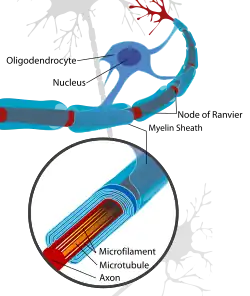

Oligodendrocytes (from Greek 'cells with a few branches'), also known as oligodendroglia, are a type of neuroglia whose main functions are to provide support and insulation to axons within the central nervous system (CNS) of jawed vertebrates. Their function is similar to that of Schwann cells, which perform the same task in the peripheral nervous system (PNS). Oligodendrocytes accomplish this by forming the myelin sheath around axons.[1] Unlike Schwann cells, a single oligodendrocyte can extend its processes to cover around 50 axons,[2] with each axon being wrapped in approximately 1 μm of myelin sheath. Furthermore, an oligodendrocyte can provide myelin segments for multiple adjacent axons.[1]

Mammalian nervous systems depend crucially on myelin sheaths, which reduce ion leakage and decrease the capacitance of the cell membrane, for rapid signal conduction.[19] Myelin also increases impulse speed, as saltatory propagation of action potentials occurs at the nodes of Ranvier in between Schwann cells (of the PNS) and oligodendrocytes (of the CNS). Furthermore, impulse speed of myelinated axons increases linearly with the axon diameter, whereas the impulse speed of unmyelinated cells increases only with the square root of the diameter. The insulation must be proportional to the diameter of the fibre inside. The optimal ratio of axon diameter divided by the total fiber diameter (which includes the myelin) is 0.6.[20]